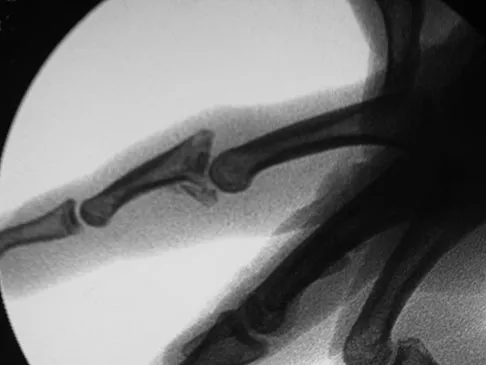

A 15-year-old girl who competes in gymnastics has immediate pain and giving way of the left elbow after falling from the uneven parallel bars and landing on her outstretched arms. Examination reveals swelling and tenderness about the elbow, especially over the medial side. Measurement of elbow motion shows 0 degrees to 125 degrees of flexion, and valgus stress at the elbow is painful. AP, lateral, and stress radiographs are shown in Figures 9a through 9c. Management should consist of

Explanation